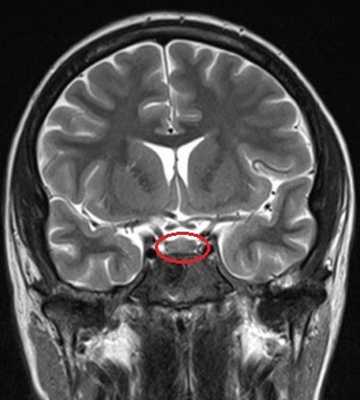

МРТ гипофиза с контрастом и без: А- гипофиз нормальных размеров (обведено кругом), В - симметричные кальцификации (стрелки)

Вопрос что лучше сделать: “МРТ гипофиза с контрастом или без?” - должен решить врач. Последний порекомендует приемлемые для получения качественных изображений характеристики аппарата: сканы, сделанные с помощью низкопольных аппаратах с открытым контуром малоинформативны. Оптимально пройти обследование на томографе с мощностью от 1,5 Тесла.

Учитывая размер гипофиза (с горошину), МРТ преимущественно выполняют с введением контрастного вещества. В качестве красителя используют растворимые соли (хелаты) гадолиния, которые не представляют опасности для организма и при накоплении тканями обеспечивают лучшую визуализацию. Побочные эффекты встречаются менее, чем у 1% людей. Контрастирование ограничивают: